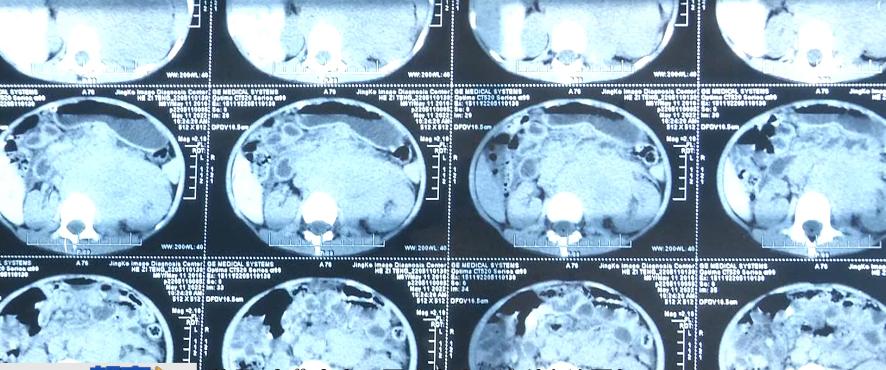

賀紅哲 賀子騰父親:去了北京也確診了為神經(jīng)母細(xì)胞瘤。第一天我們剛發(fā)現(xiàn)這個病的時候,我們拍的彩超和CT是8厘米左右,一共四天的時間,又回到內(nèi)蒙古醫(yī)院,腫瘤已經(jīng)長到了16厘米多一點,發(fā)展得非?,這個是小孩子腫瘤里面的癌王,致死率是最高的,20%的存活率。

牡丹 內(nèi)蒙古人民醫(yī)院小兒血液科主治醫(yī)師:剛開始這個腫物大概是16公分左右,這么大一個腫物,而且是骨髓轉(zhuǎn)移,這個腫物包瓤了腹腔各個血管,還有占的胰腺、左腎這些重要臟器,現(xiàn)在三個月化療以后,腫物已經(jīng)縮到了5.7公分左右,最大徑才5.7公分,療效是非常好的,家長意愿是想去上海進(jìn)行手術(shù),這樣完整切除的幾率也高一點,后續(xù)我們還有自體干細(xì)胞的回輸,放療這些。